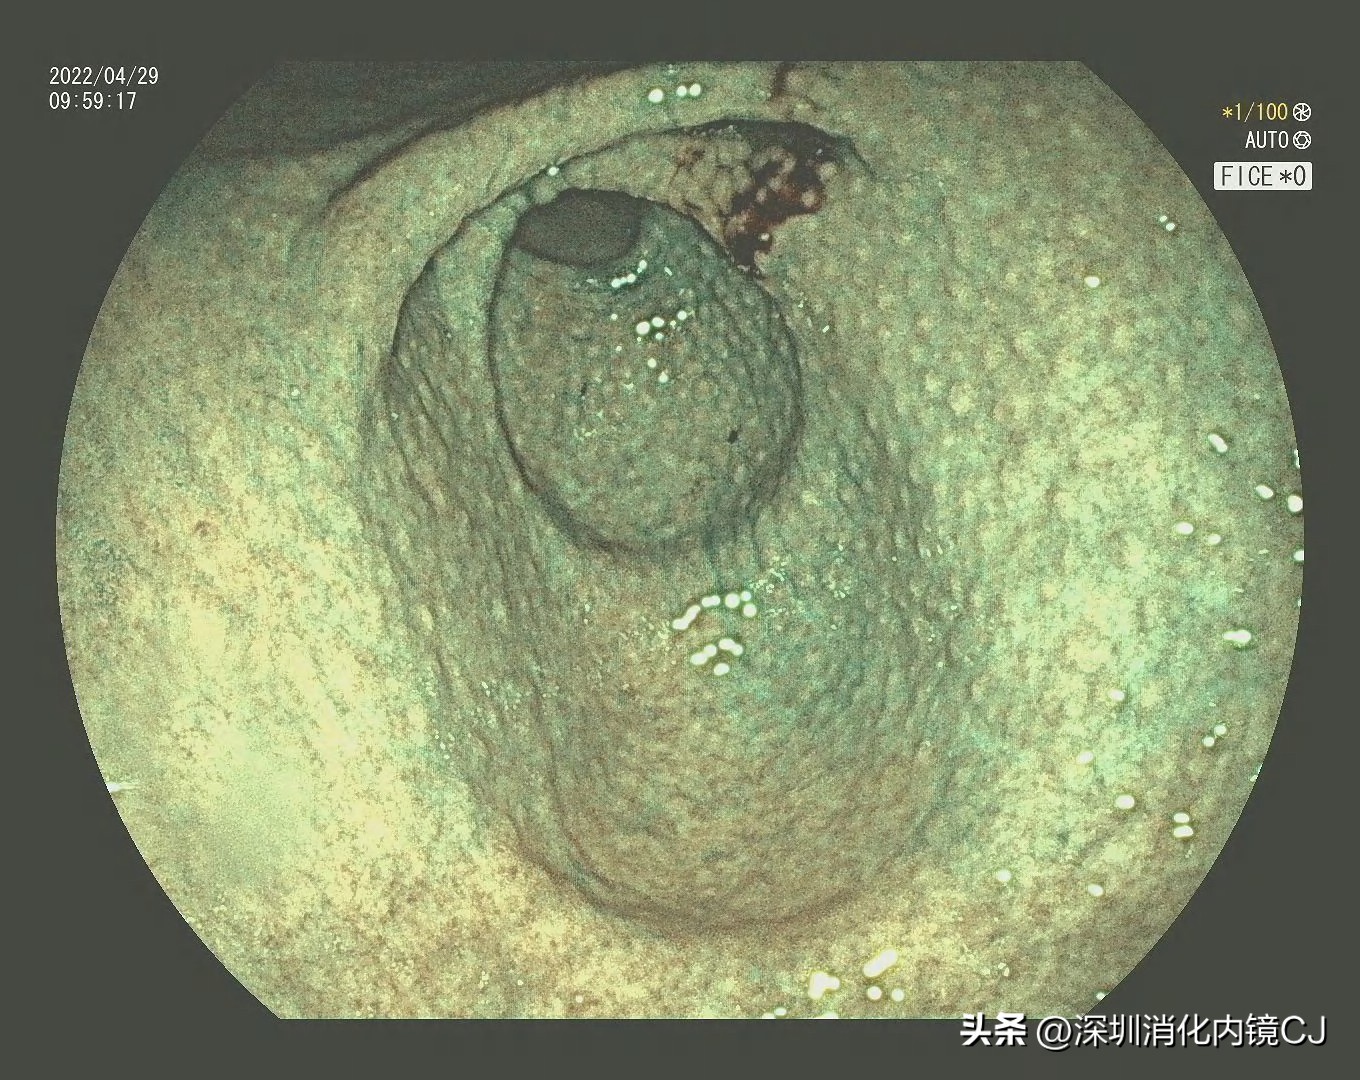

白光可见胃窦黏膜均匀细颗粒样改变

FICE染色后鸡皮样感觉增强